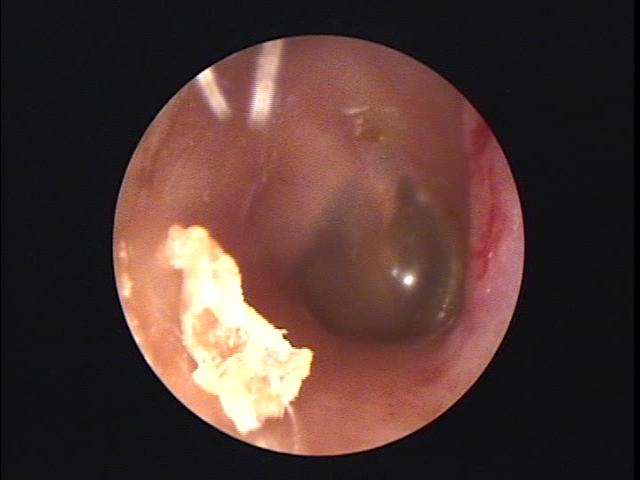

耳について | 千葉耳鼻咽喉科クリニック from chibacl.com